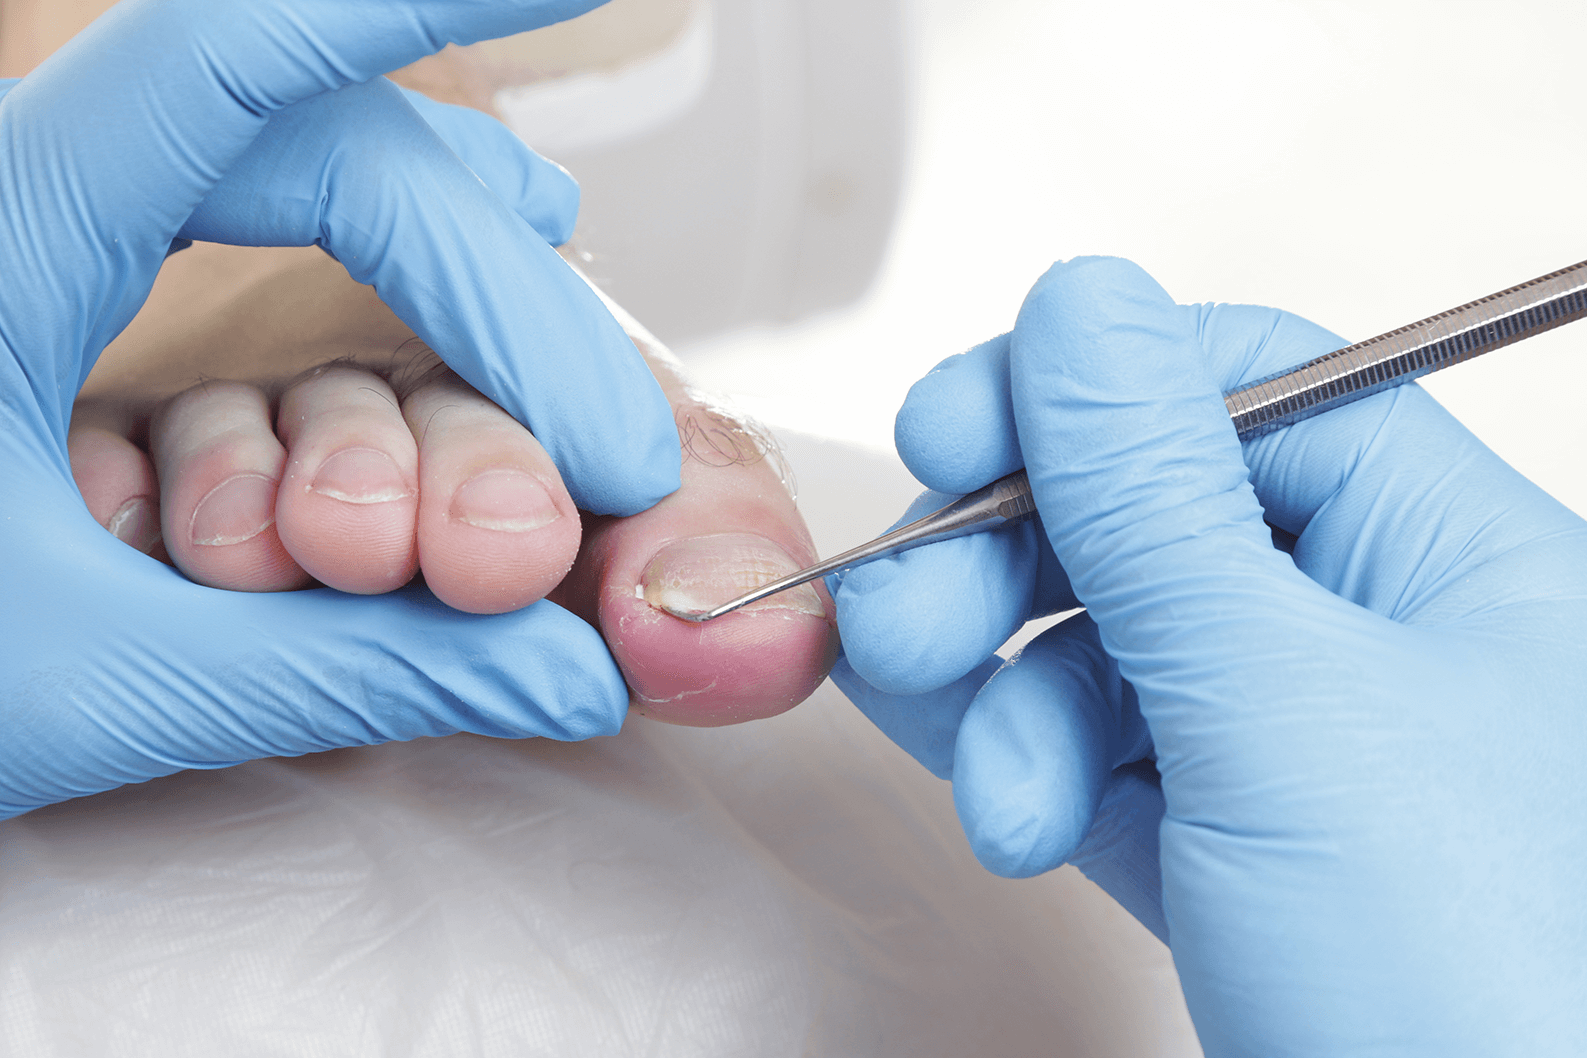

Ingrown Toenails

At Chris Garside Podiatry, we understand the agony of ingrown toenails and provide specialised care and a range of solutions to alleviate your discomfort. Trust us to help you find comfort.